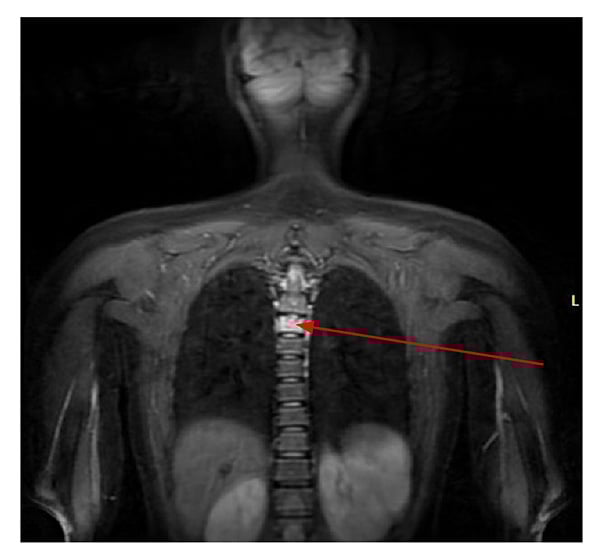

At her initial rheumatology visit, she also reported pain in the left knee and back. X-ray of the left knee revealed a metaphyseal lucency at the lateral tibia with mild surrounding sclerosis (Fig. 2). Whole-body MRI showed multiple metaphyseal regions of bone marrow edema lesions, with erosions of the left knee and right ankle consistent with CNO. Upper thoracic vertebral lesions were also found (Fig. 3).

Figure 3: Whole body MRI shows upper-thoracic vertebral lesions with marked bone marrow edema pattern.